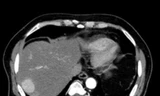

Tại khoa Ngoại Gan Mật Tụy, bác sĩ đã tiến hành siêu âm và phát hiện khối u kích thước lớn với đường kính hơn 10cm. Bên cạnh đó, kết quả xét nghiệm cho thấy các chỉ số ung thư ở người bệnh cũng tăng rất cao. Sau hội chẩn, các bác sĩ đã chỉ định thực hiện cuộc phẫu thuật nội soi cắt khối u cho bệnh nhân. Ca phẫu thuật diễn ra thuận lợi, bệnh nhân đã được cắt thành công khối u lớn ở gan. Sau mổ, sức khỏe người bệnh đã cải thiện tốt, hiện đang được tiếp tục theo dõi, điều trị.